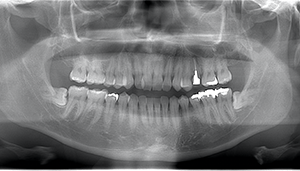

- 抜歯前写真(レントゲン)

- 抜歯前写真(CT画像)

| 抜歯内容 | 左下親知らずが横向きになって半分埋まっている状態だったため、麻酔を行い、親知らずの奥の歯ぐきに切開をいれ、歯が囲んでいる骨を削り、歯の頭の部分を削って出し、その後根の部分に器具をかけて抜歯しました。 親知らずが一部神経に近い部分があったため、術後に麻痺が出る可能性がありました。このケースでは事前にCTを撮影し、歯の位置、根の方向、神経との距離を確認していたため、幸い麻痺が出ることはありませんでした。 術後1週間経過して糸取りをして治療は終了となりました。抜歯後3日間は腫れと痛みで大変だったが、糸取りをする頃には痛みも腫れも無くなったと患者さまも喜んでおられました。 |